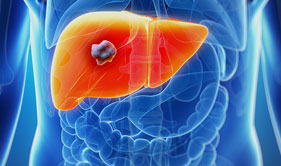

Liver Cancer

Radiofrequency Ablation

of Liver Tumors